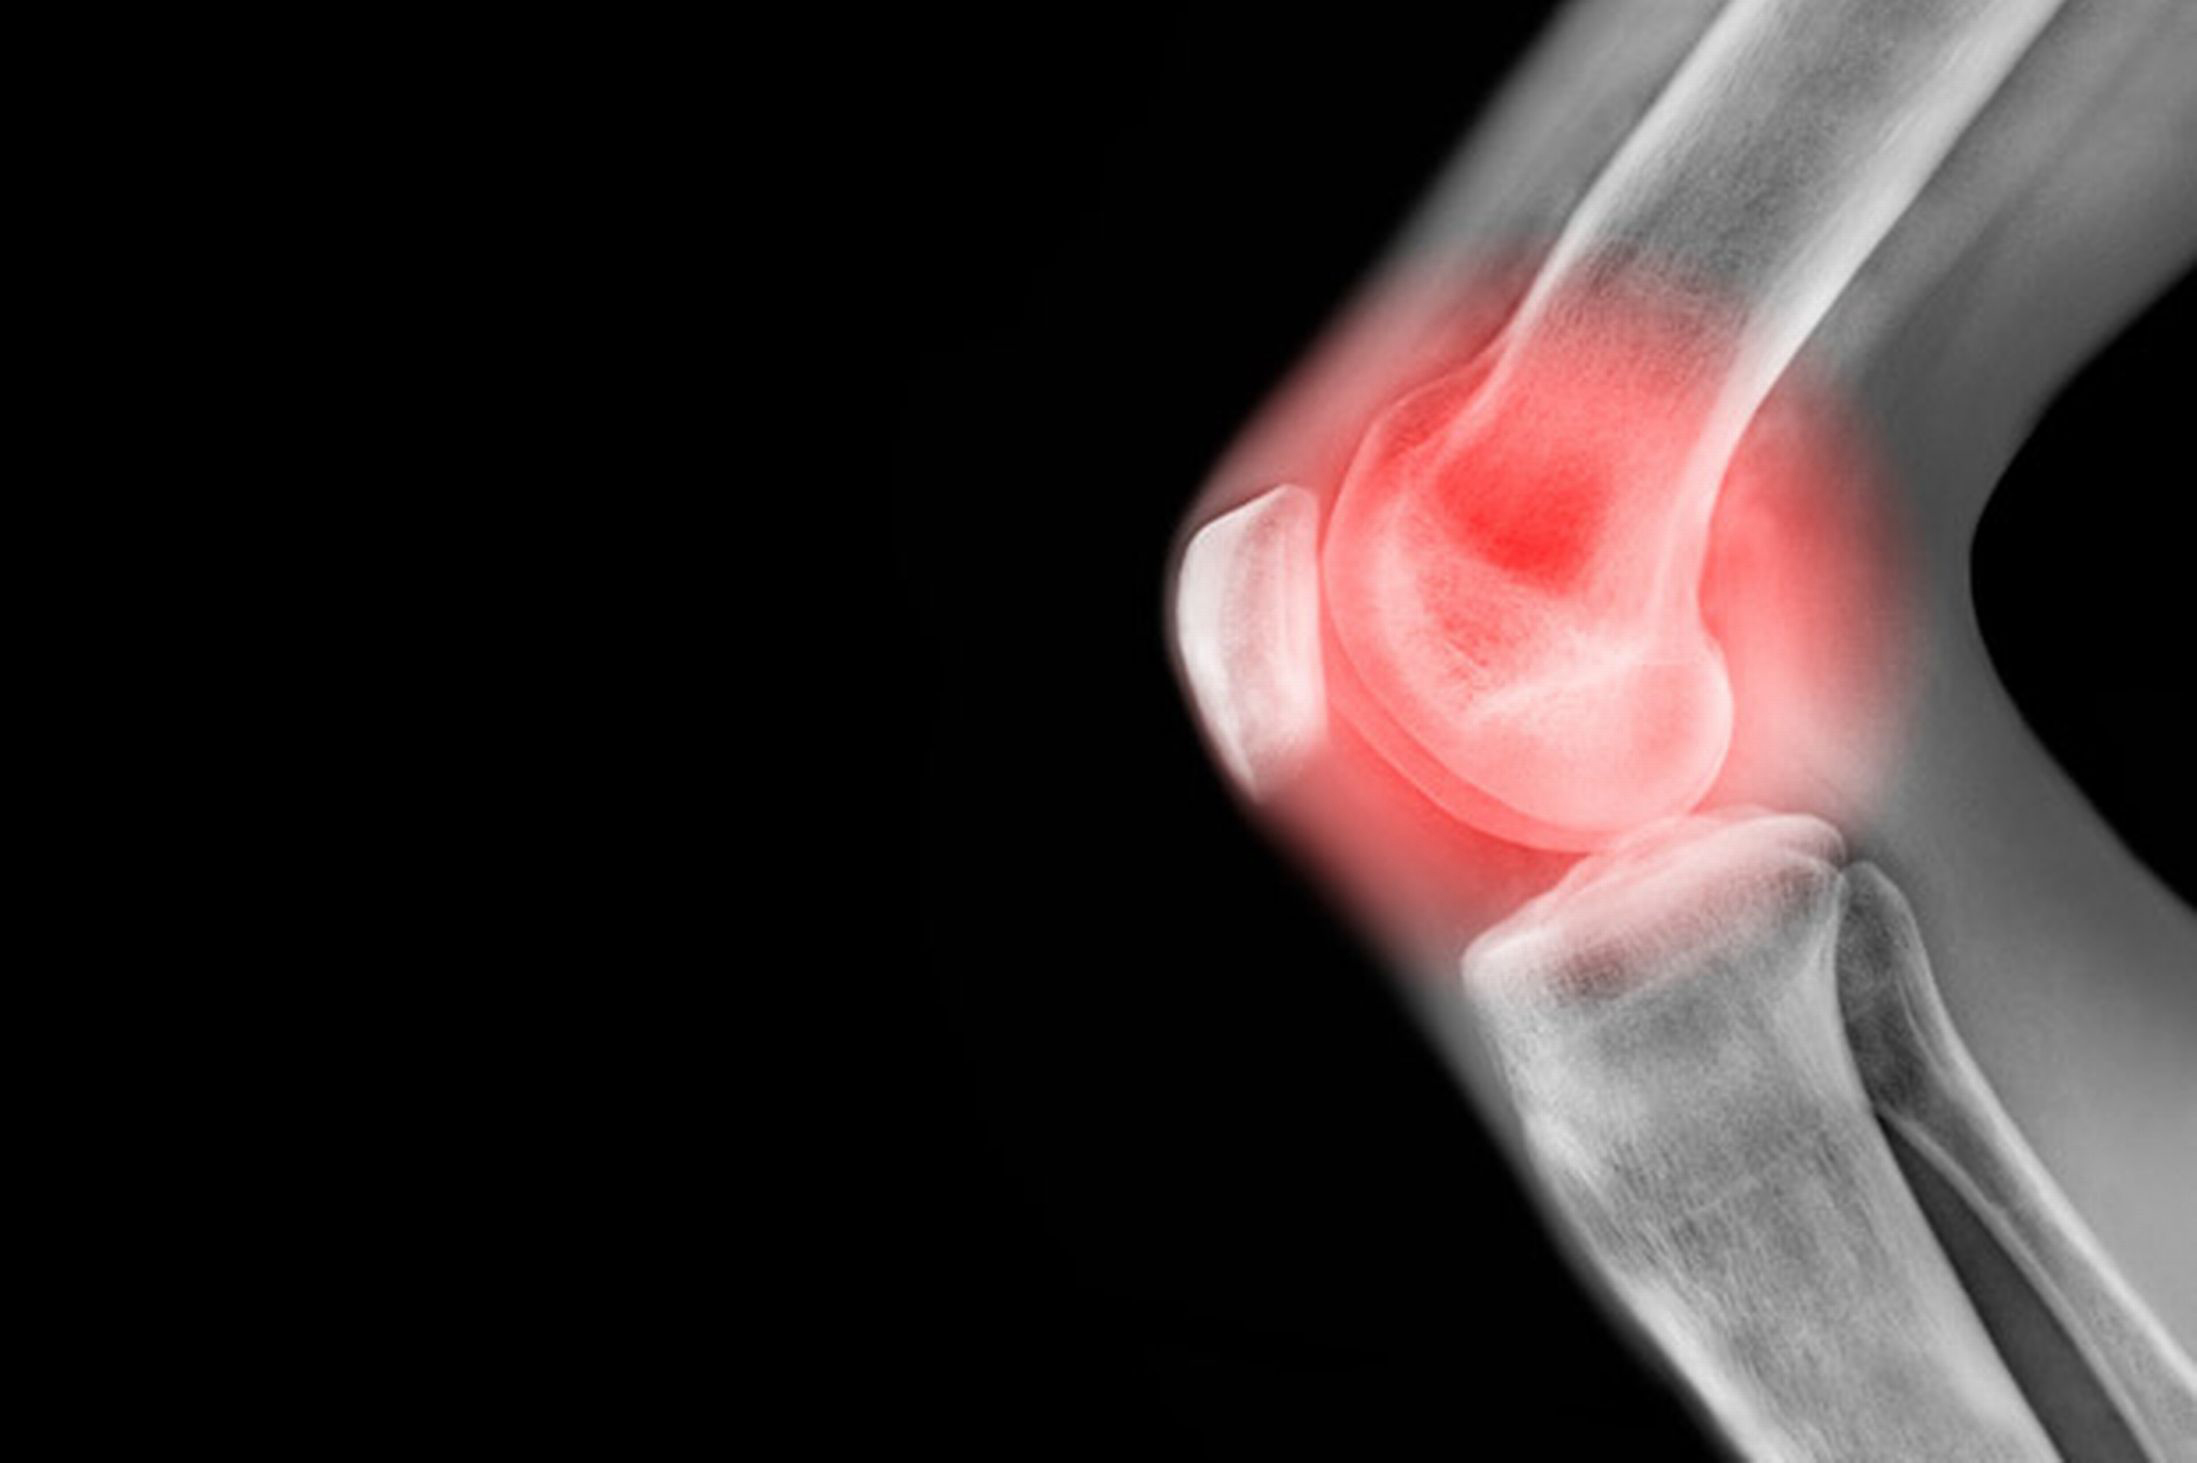

درد زانو عوامل مختلفی دارد به عنوان مثال آرتزوز، آب آوردگی مفاصل، گرفتگی عضلات از جمله مشکلات زانو هستند. بعضی از این موارد مانند گرفتگی عضلات، موقتی بوده و در گذر زمان بهبود پیدا می‌کنند. اما مصدومیت‌های دیگر می‌توانند به دردی مزمن تبدیل شوند و زندگی روزمره‌ی شما را تحت‌الشعاع خود قرار دهند.